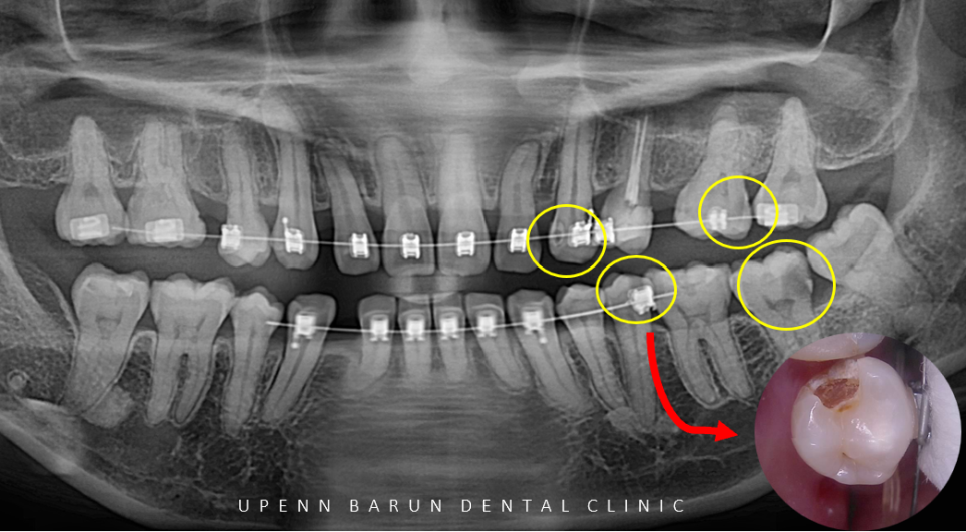

교정 전 구내 엑스레이

또한

엑스레이를 확인해보니

군데군데 충치가 있으신 상태였습니다 T^T

엑스레이 상에 까맣게 보이는 충치는

실제 충치를 제거해보면 이미 진행이 많이 된 경우가 꽤 있는데요.

충치의 범위가 신경과의 거리가 매우 가까워 신경치료가 필요한 치아가 여러개 있었지만

최대한 보존적인 방법으로

교정치료와 충치치료의 병행을 고려하여

신경치료가 불가피했던 한개의 치아를 제외 하고는

레진치료를 중점적으로 이어 나갔습니다.